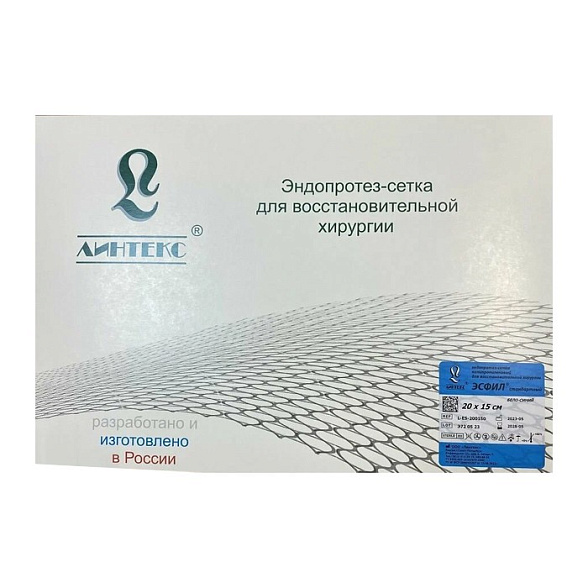

Эндопротез-сетка (сетка хирургическая) полипропиленовый для восстановительной хирургии ЭСФИЛ лёгкий, 30х10 см, Линтекс

Эндопротез-сетка полипропиленовая ЭСФИЛ лёгкий для восстановительной хирургии

| Бренд / Производитель | Линтекс (Россия) |

| Размер | 30 см x 10 см |

| Стерильность | Стерильно, индивидуальная упаковка |

| Назначение | Для ненатяжной герниопластики и реконструктивной хирургии |